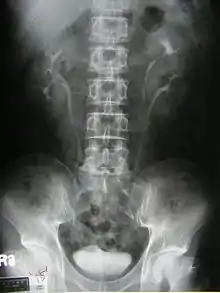

التشخيص

إن تشخيص حالة موه الكلية (الكلى المملوءة بسائل) أثناء فترة ما قبل الولادة، ليُشير إلى لزوم متابعة الفحص بعد الولادة، وأبرز عرض عند الأطفال حديثي الولادة هو عدوى المسالك البولية.

يظهر موه الكلية كجسم مجسوس (بالإنجليزية: palpable) بمنطقة البطن في الأطفال حديثي الولادة، و قد يشير إلى وجودحالب منتبذ أو وجود قيلة حالبية.